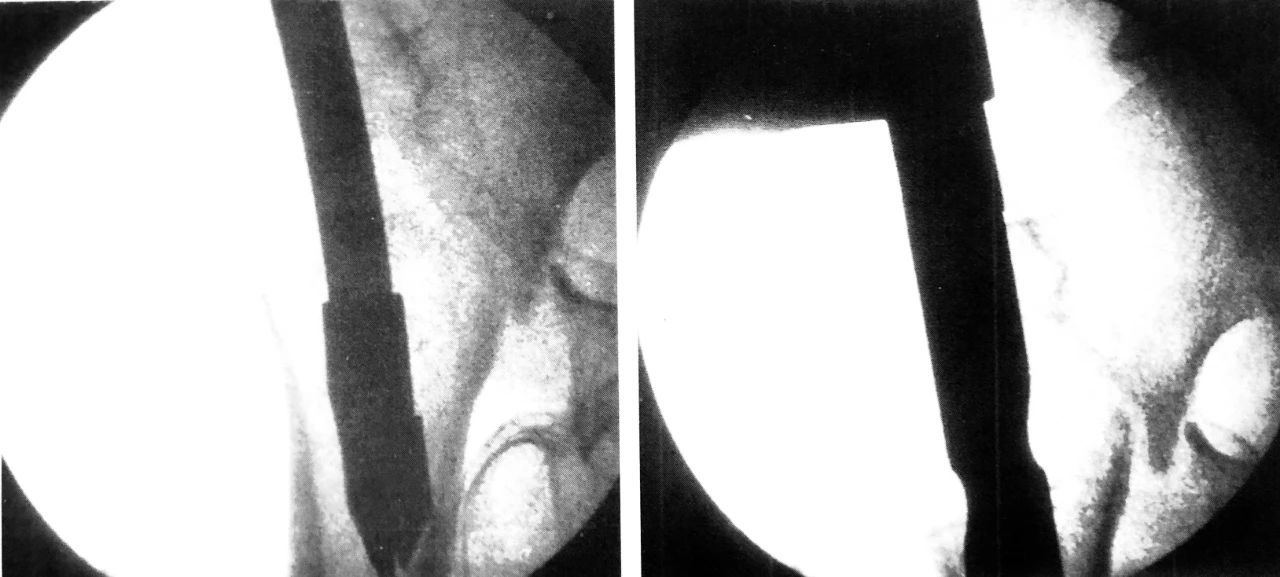

C 形臂下操作步骤,尖端开髓、插入导针

扩髓、主钉置入

正位拉力钉导针位置、侧位拉力钉导针位置

阶梯钻钻孔、正位拉力钉位置

侧位拉力钉位置、远端锁钉置入